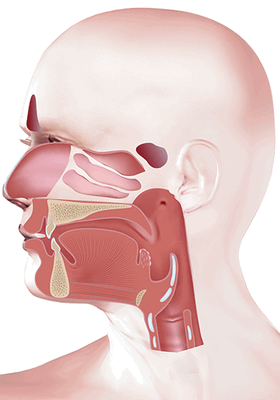

Из чего состоит лимфатическая система шеи

Лимфатическая система шеи включает в себя сосуды и узлы.

В среднем на каждой стороне шеи расположено до 75 лимфатических узлов. Снаружи узел покрывает капсула, под которой располагается субкапсулярные синусы - место куда попадает лимфатическая жидкость из приносящих лимфатических сосудов. Жидкость проходит сквозь ткань лимфатического узла, которая состоит из коркового и мозгового вещества, а затем выходит через ворота лимфатического узла и попадает в отводящие лимфатические сосуды. В итоге лимфа попадает в венозную систему в месте соустья внутренней яремной и подключичной вены.